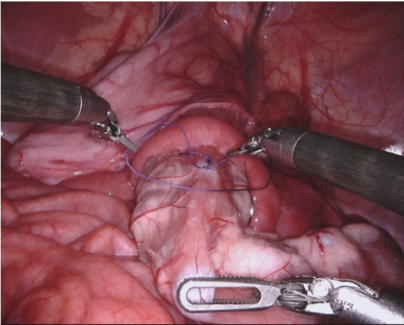

Our challenge was made up of 3 sub-problems. The first was binary instrument segmentation, where each frame was separated into da Vinci Xi instruments and a background class, which contained an ultrasound probe, surgical clips and porcine tissues. The second task was instrument part segmentation, where we scored the participants on whether they could correctly segment each articulating part of the instrument (see Fig. 3). Our final task was to segment and classify the instruments (see Fig. 4).

We provided the first 225 frames of 8 sequences as training data and kept the last 75 frames of those 8 sequences as test data. 2 of the full 300 frame sequences were kept as test sequences. Test labels were kept hidden from the participants. Our datasets contain 7 different robotic surgical instruments. The Large Needle Driver, Prograsp Forceps, Monopolar Curved Scissors, Cadiere Forceps, Bipolar Forceps, Vessel Sealer and additionally a drop-in ultrasound probe, which is typically held in the jaws of the Prograsp Forceps instrument. Samples from the training datasets are depicted in Fig. 2 and examples of the different instrument types are shown in Figure 3 and 4.

IV-D Type Segmentation

The final challenge was to identify each instrument type from the list of Large Needle Driver, Prograsp Forceps, Monopolar Curved Scissors, Vessel Sealer, Fenestrated Bipolar Forceps and Grasping Retractor (see Fig. 4). Only 6 teams participated in this challenge, due particularly to the significant increase in difficulty in recognizing many of the da Vinci instruments from one another.